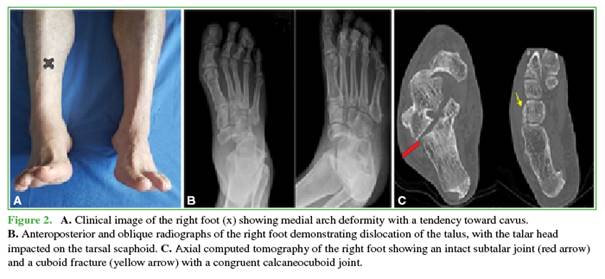

He was initially evaluated by a general practitioner, who referred him to Orthopedics for outpatient consultation rather than emergency care. He presented late to our Department, with lameness, residual edema, pain, and medial deformity in the midfoot, as well as a tendency toward supinatus and cavus. He had limited inversion, eversion, and plantar flexion movements.

Initial radiographs showed a medially rotated talonavicular dislocation with impaction of the navicular on the anterior articular surface of the talus and a fracture of the cuboid. A CT scan was performed to identify associated injuries and assist in surgical planning (Figure 2). Given the chronic nature of the case and the presence of an osteochondral injury, we opted for open reduction of the dislocation, followed by stabilization with arthrodesis and bone graft. The patient signed an informed consent form authorizing the use of his images.